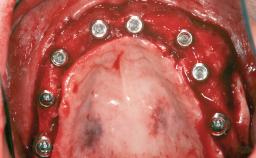

A 47-year-old Caucasian woman with a single-tooth edentulous space at the site of the left maxillary canine was referred for treatment. She had undergone traumatic extraction of this impacted canine several months before referral. Her chief complaint was the dissatisfying appearance of her smile. The patient desired a stable and esthetic rehabilitation of the site. Her dental history showed no evidence of periodontal disease or bruxism. She had no systemic diseases, was not taking any medications, and did not smoke. The extraoral examination revealed a high lip line and an inadequate soft-tissue volume at the defective canine site. Large black triangles were visible between the canine and its adjacent teeth.

Bone Augmentation Staged|Vertical

Augmentation Materials Autogenous chips|Membrane

Bone Volume Horizontally and vertically sufficient Horizontally deficient Deficient vertically or deficient vertically AND horizontally

Bone Volume Deficient vertically or deficient vertically AND horizontally